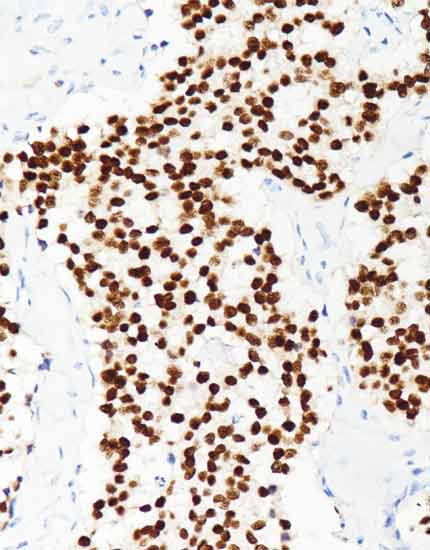

产品名称:NKX2.2

产品编号:RMA-0747

阳性部位:细胞核

图片描述:

神经内分泌癌,NKX2.2染色,细胞核阳性